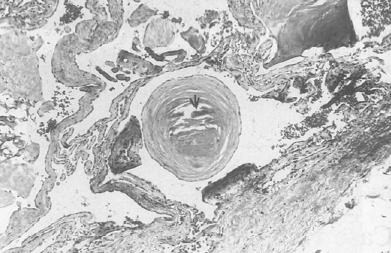

On histological examination the lesion was found to be a haemangioma. Some of the vascular spaces within it contained calcifed thrombus (Fig. 4).

Fig. 4 - Histological section of the haemangioma. The arrow indicates the calcified thrombus.